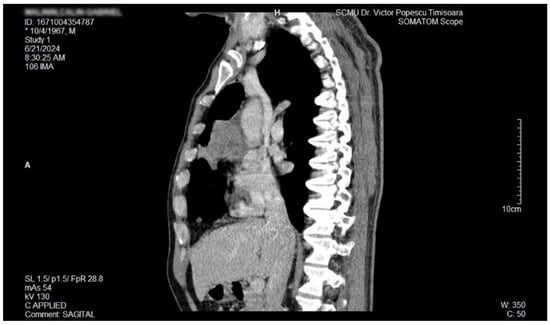

Figure 3.

Contrast thorax CT: large right midthoracic tumor with mediastinal extension.(axial view.

Figure 4.

Contrast thorax CT: large right midthoracic tumor with mediastinal extension (coronal view).

Figure 5.

Contrast thorax CT: large right midthoracic tumor with mediastinal extension (sagittal view).

The proposal for H. pylori eradication treatment was initially postponed by the patient. However, the patient received symbiotics in order to alleviate the gut microbiota dysbiosis and also DAO supplementation, aiming at reducing the systemic effects of bacterial histamine overproduction. Further imaging studies were, however, ordered in the context of persistent, treatment-resistant pruritus that lasted for more than 6 weeks and eventually became suspicious for a malignancy. So that thorax and abdomen computed tomography (CT) were recommended and performed soon after, on 21 June 2024. As depicted in Figure 3, Figure 4 and Figure 5, a large right mid-thoracic tumoral formation with mediastinal extension of 7.8 cm/5 cm and a satellite lymph node of 7 mm placed in the anterior aspect of the upper right pulmonary lobe were discovered. The image was considered highly suspicious of lymphoma or pulmonary malignancy.